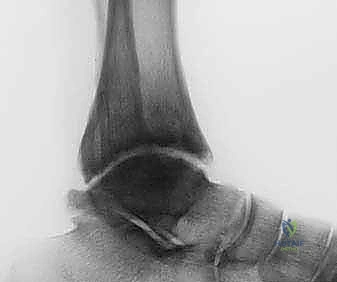

- الأشعة السينية (X-rays) مع الوقوف: لتقييم المسافة المتبقية من المفصل وتحديد درجة الخشونة ومحور الساق.

- الأشعة المقطعية (CT Scan): للحصول على صورة ثلاثية الأبعاد للعظام، واكتشاف أي تكيسات عظمية (Bone cysts) أو نتوءات عظمية (Osteophytes).

أثناء العملية، يقوم الدكتور هطيف بإبعاد حلقة الساق عن حلقة القدم تدريجياً وببطء باستخدام قضبان ملولبة، حتى يصل إلى مسافة تشتيت تبلغ حوالي 5 إلى 6 ملليمترات. يتم التأكد من هذه المسافة عبر الأشعة السينية داخل غرفة العمليات.

- زيادة مساحة المفصل: تظهر الأشعة السينية بوضوح اتساع المسافة بين عظام الكاحل، وهو دليل قاطع على تجدد النسيج الغضروفي.